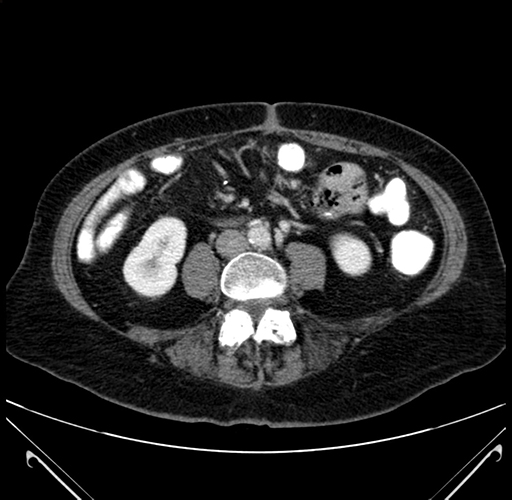

Axial Venous

Coronal Venous

Based on your CT findings, which issue(s) would give reason for "planned slowing down moment(s)" in this case?

Considering a standard right hepatectomy procedure, what step(s) of the operation would you do differently in this case?